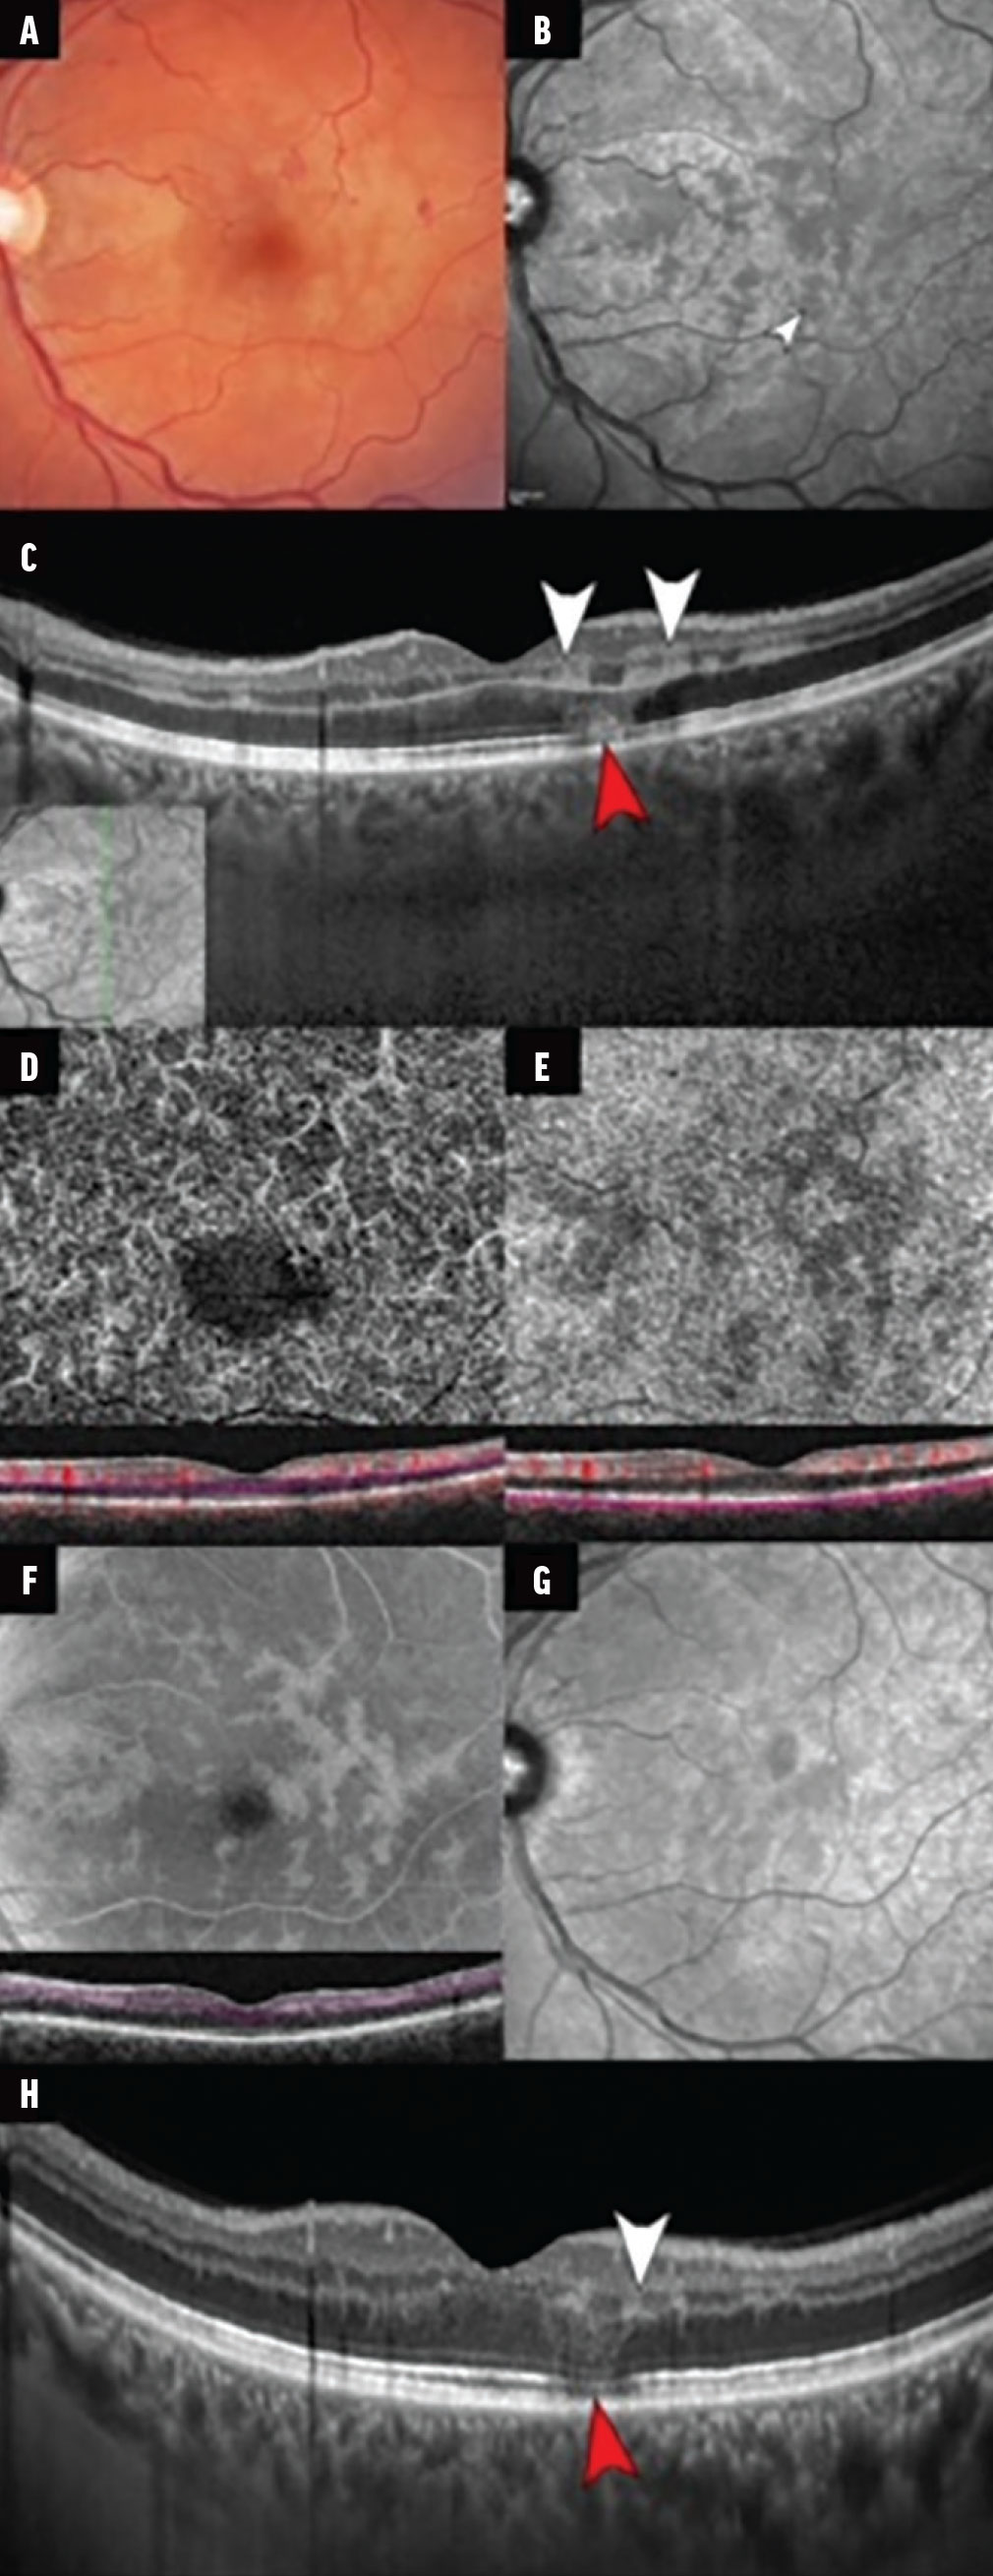

Нещодавно стало відомо про випадки уражень PAMM та AMN на одному оці, що вказує на загальну патологію (малюнок 2). Був виявлений зв’язок PAMM та AMN в очах з оклюзією вени сітківки (CRVO, hemi-RVO) та з ретинопатією Пурчера.  При ретинопатії Пурчера, всі три види ураження сітківки були виявлені в ураженому оці, включаючи внутрішній інфаркт сітківки (тобто ватні плями), інфаркт середньої сітківки (тобто PAMM) і зовнішнє руйнування сітківки (тобто AMN).

Малюнок 2. Клінічний випадок цього пацієнта демонструє збіг PAMM та AMN в оці з CRVO. Кольорова фотографія очного дна показує перивенулярне відбілювання сітківки в макулі з розсіяними крововиливами в сітківку та венозним розширенням, що відповідає CRVO (A). Зображення в ближньому інфрачервоному діапазоні показує перивенулярну гіпорефлективність,, що відповідає ураженням PAMM (B; біла стрілка). Вертикальне В-скан спектрального ОКТ показує гіперрефлективні смугоподібні ураження, які переважно охоплюють INL і поширюються на сусідні IPL/OPL відповідно до PAMM (C). Зверніть увагу на характерне гіперрефлективне ураження, що відповідає AMN, присутнє в ONL і переходить в HFL. Зображення NIR вказує на розташування B-скану спектрального ОКТ (C, вставка).En face OCTA DCP показує численні зони відсутності декореляційного сигналу, які локалізуються разом із ураженнями PAMM на OCT (D). B-скан поперечного перерізу спектрального ОКТ вказує на сегментацію (рожеві лінії) відповідної OCTA на рівні DCP (D, вставка). OCTA-зображення хоріокапілярів en face показує ділянки втрати сигналу потоку, імовірно пов’язані з тіньовими артефактами від розташованих вище уражень PAMM (E). B-скан поперечного перерізу спектрального ОКТ вказує на сегментацію (рожеві лінії) відповідної OCTA на рівні хоріокапіляра (E, вставка). Контрольна ОКТ через 1 місяць, сегментована на рівні DCP, показує ослаблення папоротеподібного малюнка (F). Контрольне NIR-зображення через 1 місяць демонструє зниження гіперрефлективності ураження PAMM (G). Контрольна ОКТ ділянки макули через 1 місяць показує подальше витончення INL, що відповідає інфаркту INL, у зонах попередніх уражень PAMM (H; біла стрілка). Попри те, що гіперрефлективність ураження AMN частково вирішена, існує стійкість порушення EZ-IZ (червона стрілка). Зображення люб’язно надане Iovino C, Au A, Ramtohul P, et al. Coincident PAMM and AMN and insights into a common pathophysiology. Am J Ophthalmol.